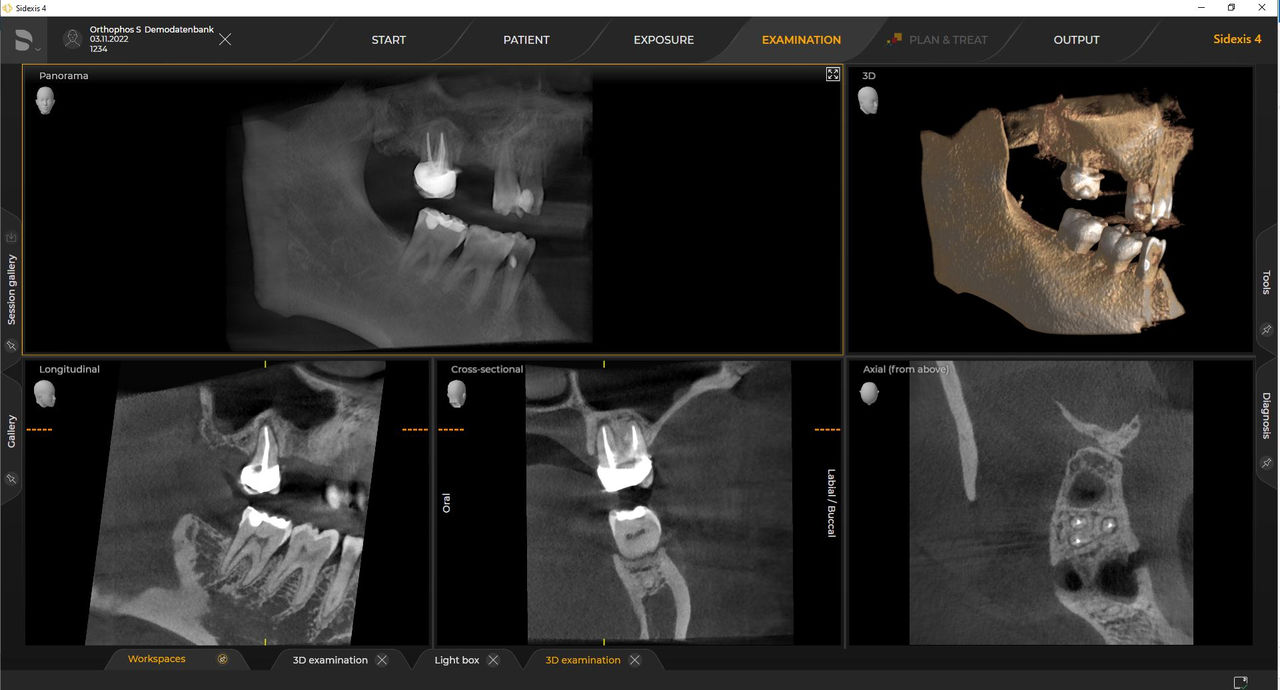

Dentsply Sirona-röntgeneenheden werken uitsluitend met Sidexis 4. Toch is de gegevensmigratie van Sidexis XG naar Sidexis 4 heel eenvoudig. Sidexis 4 zorgt voor een volledige digitale ervaring met de nieuwste tools

Orthophos S 2D maakt een 3D-upgrade mogelijk. Axeos is een speciale hybride unit. De Orthophos E heeft deze optie niet.